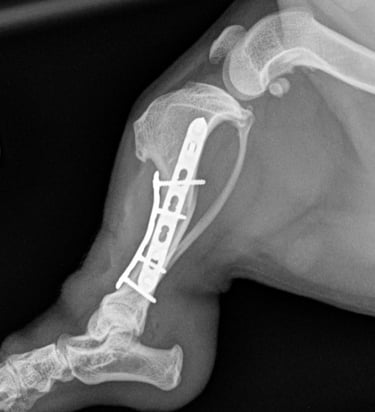

Tibia fracture - Mini Dachshund, 2y, female

This small and sweet 5.4 kg female patient sustained a lameness after playing in the garden allotment. Orthogonal radiographs revealed a surgical, long oblique spiral mid-diaphyseal fracture of the left tibia (Fig. 1 and 2).

Fig. 1